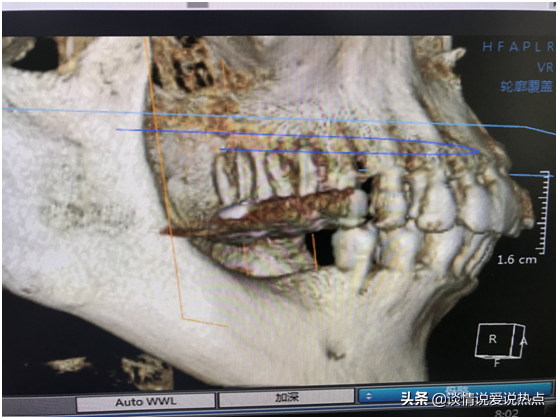

下圖是我現(xiàn)在右邊的牙齒,上頜做了根管調(diào)節(jié)戴冠,下頜缺失要種兩顆。醫(yī)生說(shuō)我經(jīng)常用上頜咬東西,上頜有一顆戴冠的已經(jīng)伸長(zhǎng)了,如果我再不管,三顆都會(huì)伸長(zhǎng)。